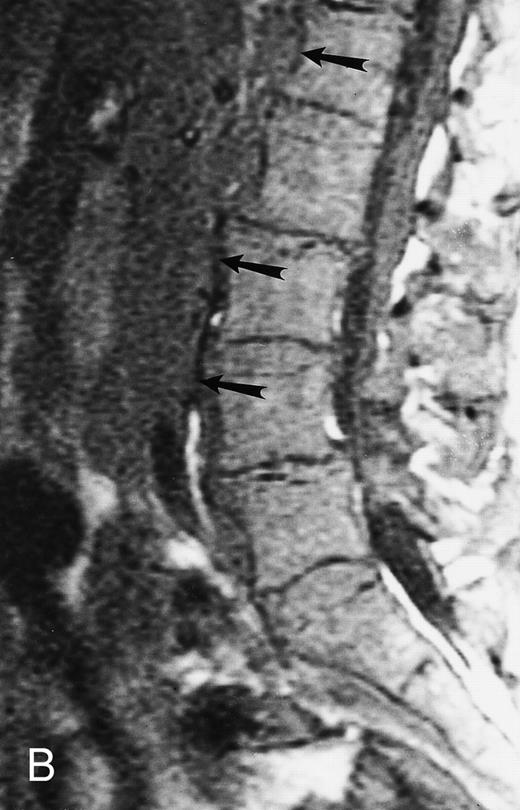

Diffuse MR pattern of abnormal marrow in a 29-year-old man with AML: T1-weighted sagittal (500/10, TR/TE) (A), T2-weighted, fat-suppressed fast spin echo sagittal (5000/96, TR/TE, ET 16) (B), and enhanced T1-weighted sagittal (500/10, TR/TE) (C) MR images of the thoracic spine. The abnormal vertebral bodies in (A) are dark and isointense to the intervertebral discs and in (B) they become bright. In (C), the abnormal marrow enhances and the vertebrae become brighter than the discs. Note extraosseous mass (arrowheads) in the posterior epidural space with preservation of the bony cortex.